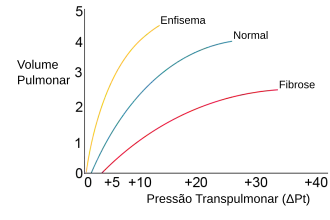

Complacência Pulmonar

A complacência pulmonar é a característica que determina a capacidade de expansão do pulmão. Quanto maior a complacência, mais fácilmente expandir-se-á o pulmão para uma dada variação em pressão.[9] Ou seja,

Os principais fatores que controlam a complacência pulmonar são relacionadaos às forças constitutivas do pulmão, sobretudo a força de retração elástica e a ação da tensão superficial da água que reveste os alvéolos. A junção dessas forças forma a força de retração pulmonar, que resiste à expansão do pulmão durante a inspiração e provoca a deflação pulmonar durante a expiração. Com a distensão do pulmão durante a expansão, a força de retração elástica se torna maior. Assim, a complacência diminui conforme o volume pulmonar é aumentado durante a inspiração.[10]

A complacência pulmonar depende, portanto, da intensidade da força de retração pulmonar, uma vez que, se a força for muito intensa, o pulmão terá mais dificuldade de se expandir, já que os músculos da respiração terão que vencer uma força maior que o normal.[11] Este é o caso das fibroses intersticiais pulmonares, em que o aumento da deposição de elastina no pulmão leva ao aumento da força de retração elástica e dificulta a expansão pulmonar (ver gráfico). Bebês prematuros nascidos antes da 24ª semana de Idade gestacional não desenvolveram as células pneumócitos II, responsáveis por produção de surfactante pulmonar, e desenvolvem uma tensão superficial muito maior que o normal, provocando o aumento da força de retração pulmonar e colapsando os alvéolos, uma condição denominada atelectasia.[12]

Quando, ao contrário, há redução da força de retração pulmonar, como na efisema, por destruição do interstício pulmonar, a complacência aumenta, uma vez que a resistência à expansão pulmonar será diminuída. Isso não é vantajoso, pois apesar de ser possibilitar a expansão mais rápida do pulmão, as forças de retração pulmonar são as principais responsáveis pela expiração. Dessa forma, esses pacientes têm dificuldade de expirar e muitas vezes não conseguem completar o ciclo respiratório antes de realizar outra inspiração. Ademais, devido à diferença de pressão local do pulmão, ocorre fechamento prematuro das vias aéreas nesses pacientes, com formação de bulhas respirtórias características.[13]